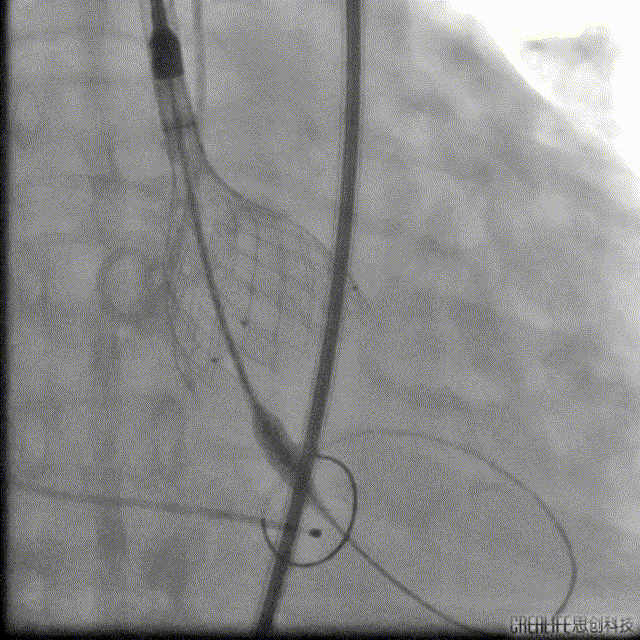

VenusA32瓣膜瓣中瓣

最后一枪造影